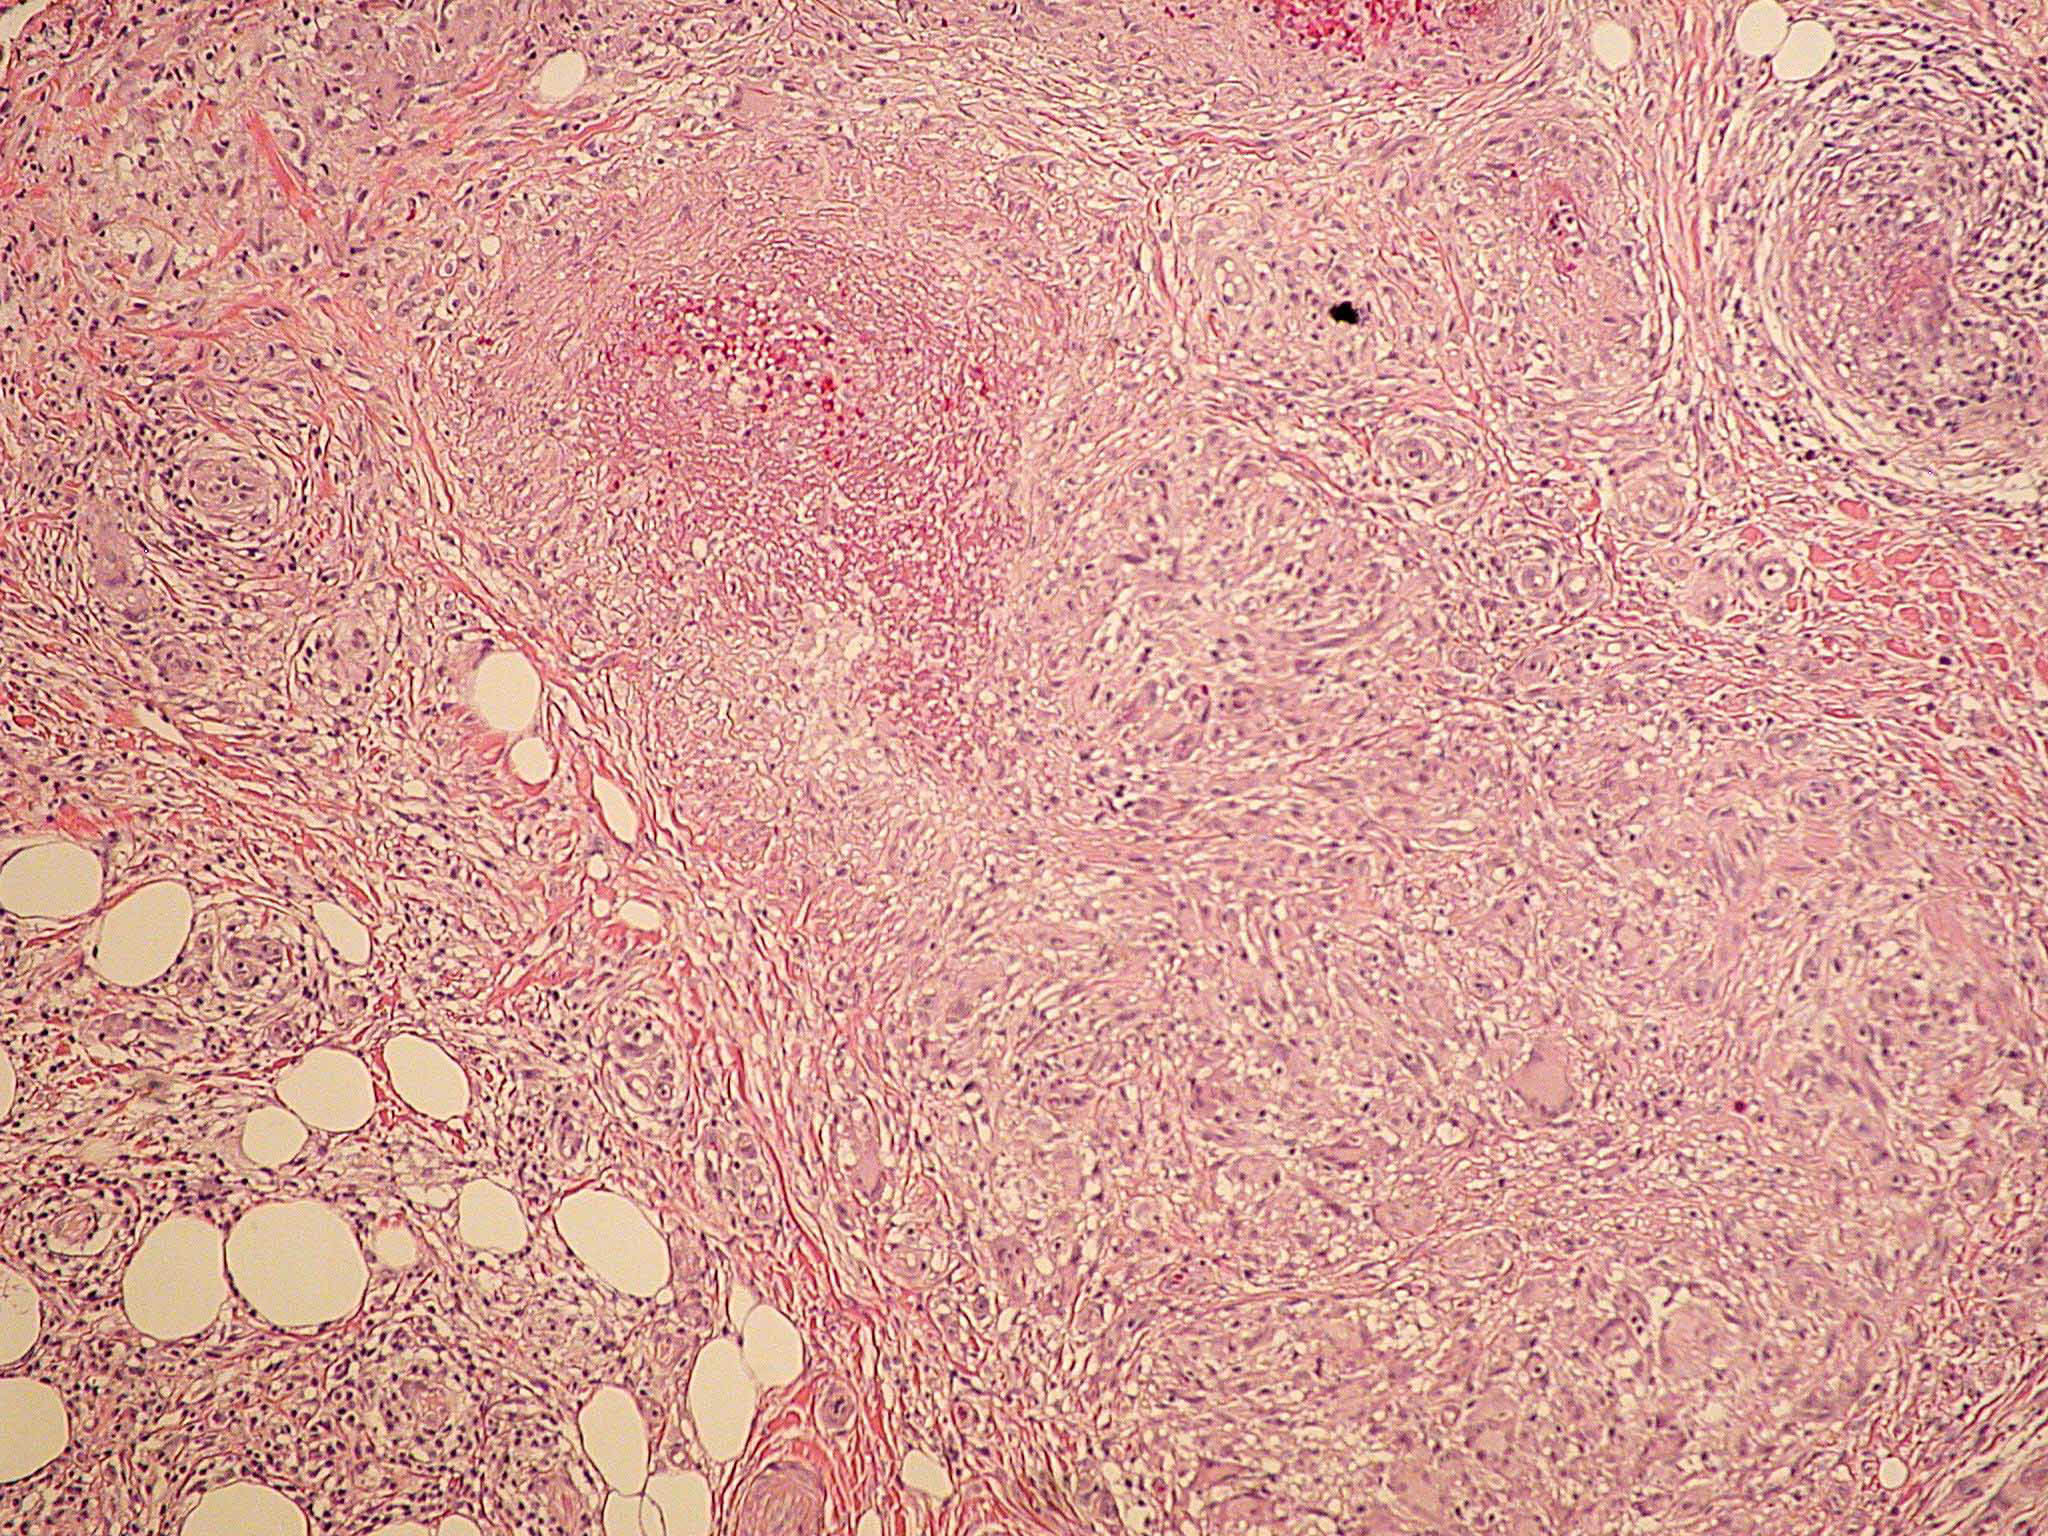

Nodular vasculitis = التهاب الاوعية العقيدي